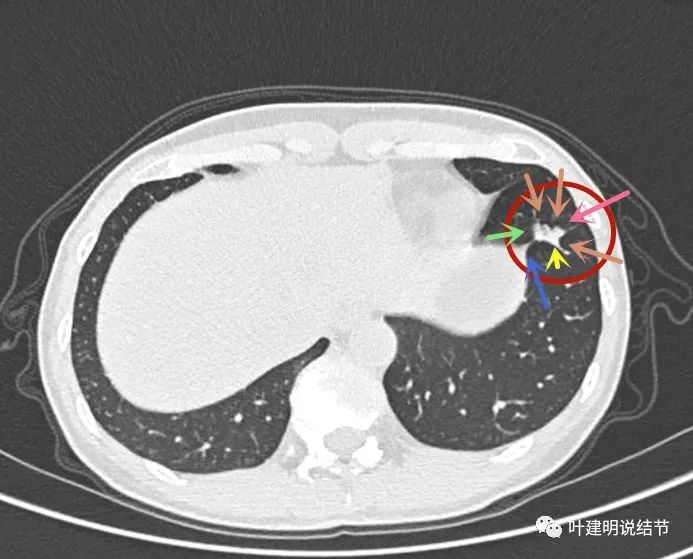

2022年2月的胸部薄层CT图像:

主病灶位于左下叶,见实性成分为主(粉色箭头),边缘少许磨玻璃成分(绿色箭头),有毛刺牵拉(蓝色箭头),病灶分叶明显(砖色箭头),局部边缘特别整齐(黄色箭头,小叶间隔?)。